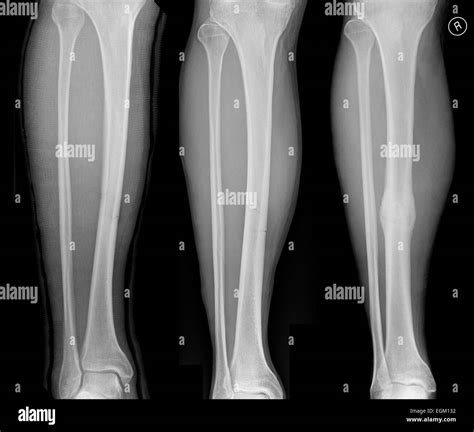

Tibia And Fibula Fracture Recovery Time